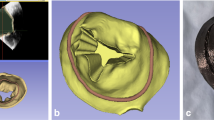

Due to the complexity and multi-layered ultrastructure of the mitral valve leaflets, we created both homogeneous and multi-material printed samples of mitral leaflets. The homogeneous ‘Leaflet A’ samples were fabricated of Agilus shore 27 (20 mm × 5 mm × 1 mm). The ‘Leaflet B’ samples were comprised of two 1 mm thick layers (20 mm × 5 mm × 2 mm), in which one layer was fabricated with Agilus shore 27 and the second layer with Agilus shore 50. The ‘Leaflet C’ samples were made of a 1 mm thick inner layer printed with Agilus shore 27, and a 0.4 mm thick outer shell printed of Agilus shore 70. Patient-specific mitral valve leaflets were reconstructed from computed tomography (CT) images of patient mitral valves using the imaging processing platform Mimics (Materialize, Belgium). The CT images were acquired using Siemens Force System with optimal contrast protocol. Image resolution was 512 × 512 pixels, with slice thickness of 0.6 mm.

These leaflets, designated as sample group ‘Leaflet D’, were comprised of an inner layer printed using Agilus shore 27 and an outer shell printed using Agilus shore 70 and had a combined leaflet thickness that varied between 1 and 3 mm (as shown in Fig. 2). The patient-specific geometry of the leaflets and their irregular thickness was preserved.

The ‘Chordae A1’ and ‘Chordae A2’ sample groups were homogeneous cylindrical samples printed of Agilus shore 30 and shore 70, respectively. The ‘Chordae B1’ samples had spiral reinforcements, the ‘Chordae B2’ samples had sinusoidal reinforcements, and the ‘Chordae B3’ samples had rope-like reinforcements. The cylindrical base for all these three groups was printed of Agilus shore 70 and the reinforcement fibers were printed of Agilus shore 95. The printed annulus, leaflet, and chordae designs are summarized in Fig. 2.